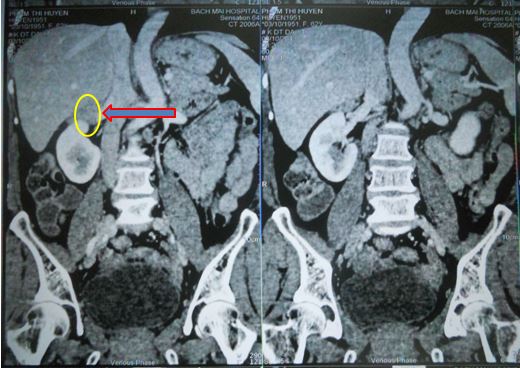

Trên hình ảnh cắt lớp vi tính ổ bụng cho thấy: Hình ảnh khối tổn thương tại tuyến thượng thận phải đã thu nhỏ kích thước với đường kính u: 18x16mm

Hình 3. Hình ảnh khối tổn thương tại thượng thận phải trên phim chụp cắt lớp vi tính lát cắt ngang

Hình 4. Hình ảnh khối thượng thận phải trên phim chụp cắt lớp vi tính lát cắt đứng ngang